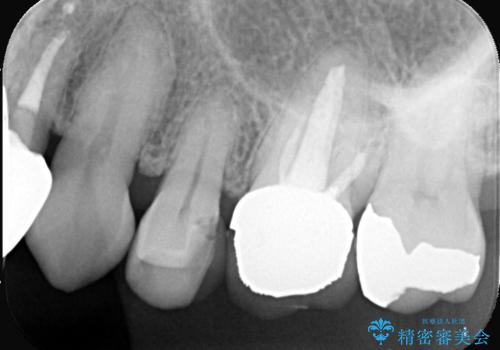

- 「以前治療した被せ物の色が気になる」「最近しみるようになった」との主訴で来院されました。診察の結果、古い被せ物の周囲に段差ができており、そこから虫歯が進行している状態でした。また、色も経年劣化により周囲の歯と調和が取れておらず、笑ったときに目立つとのお悩みもありました。

まず古い被せ物を慎重に取り除き、中に広がっていた虫歯を丁寧に除去しました。歯質の状態を確認したうえで、必要な部分には土台(コア)を補強し、セラミッククラウンを装着する準備を整えました。